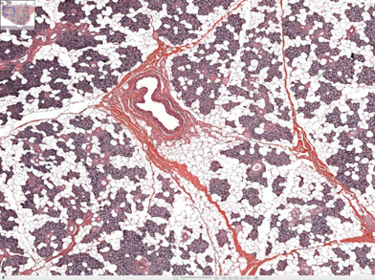

alveolar microphages

dust cells within macrophages in lungs (black dots)